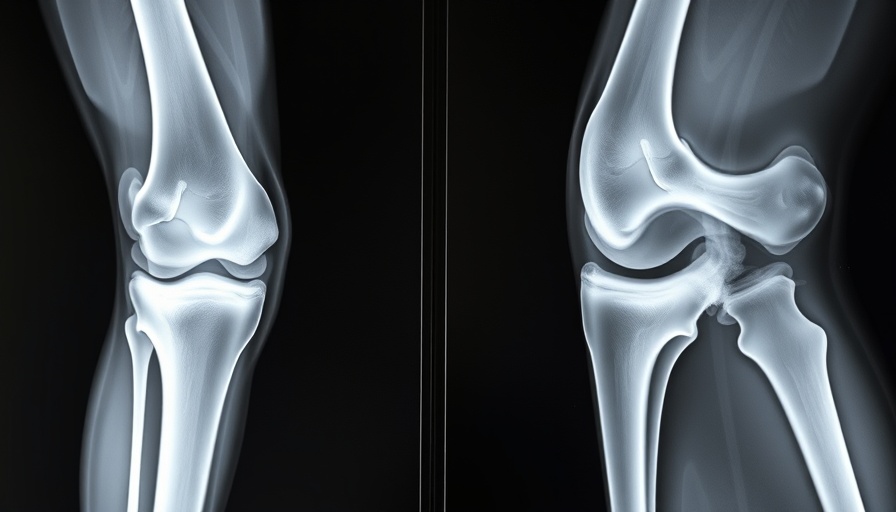

A recent case exposed the intricate relationship between diagnostics and patient experience, particularly when a woman presented with debilitating knee pain, revealing striking 'golden threads' within her joints. This unusual find highlights an important intersection between emerging medical technologies and traditional diagnostics, raising questions regarding the accuracy and depth of our current healthcare systems.

The golden threads in question refer to advanced imaging techniques that have revealed structural abnormalities not typically visible in conventional scans. These anomalies could be synthetic threads associated with an implant or possibly markers of an underlying condition like synovial osteochondromatosis or a rare inflammatory disorder. For patients, such discoveries can drastically alter treatment plans and prognoses, pressing the need for thorough evaluation processes in diagnosing joint pain.

In this story, we see how advancements in imaging—like MRI and CT scans—are revolutionizing the approach to diagnosing musculoskeletal disorders. Traditional methods sometimes fall short, which leads to misdiagnoses or unnecessary surgical interventions. The emergence of AI-assisted diagnostic tools can enhance radiological interpretations, providing doctors with robust data to form accurate conclusions.